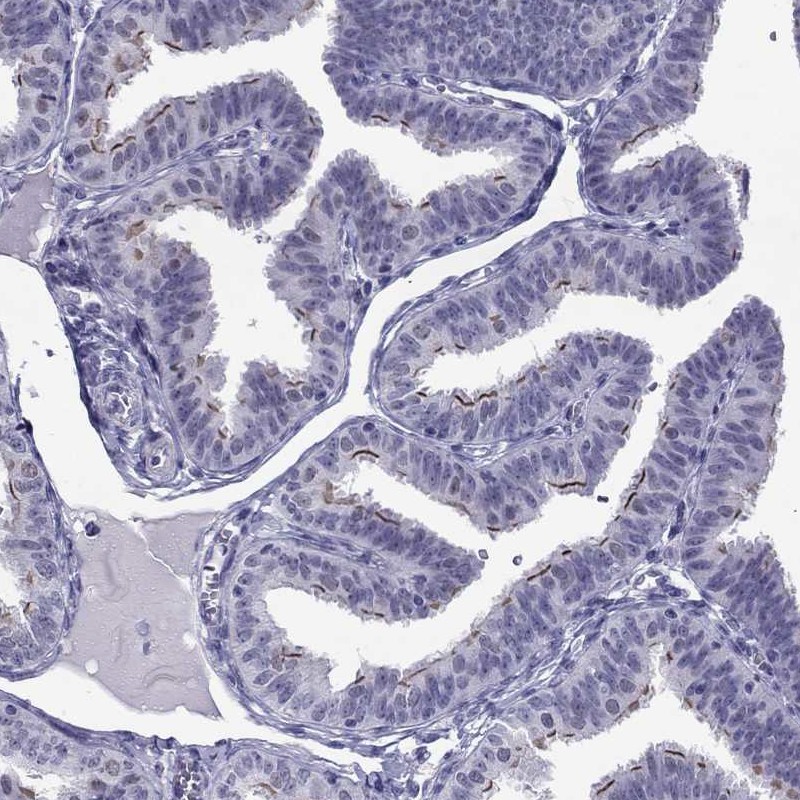

Immunohistochemistry analysis in human fallopian tube and prostate tissues using Anti-CROCC2 antibody. Corresponding CROCC2 RNA-seq data are presented for the same tissues.